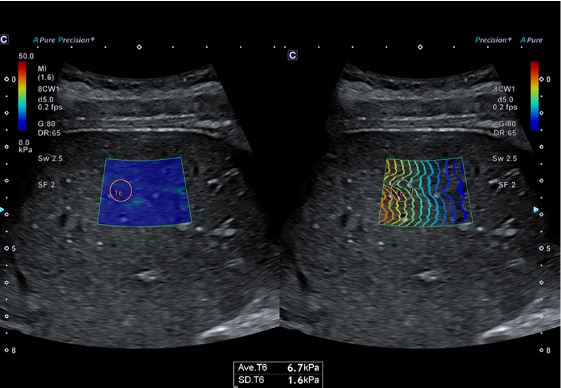

Еластографія зсувної хвилі (SWE) візуалізує швидкість зсувної хвилі та еластичність тканини для аналізу фіброзу печінки.